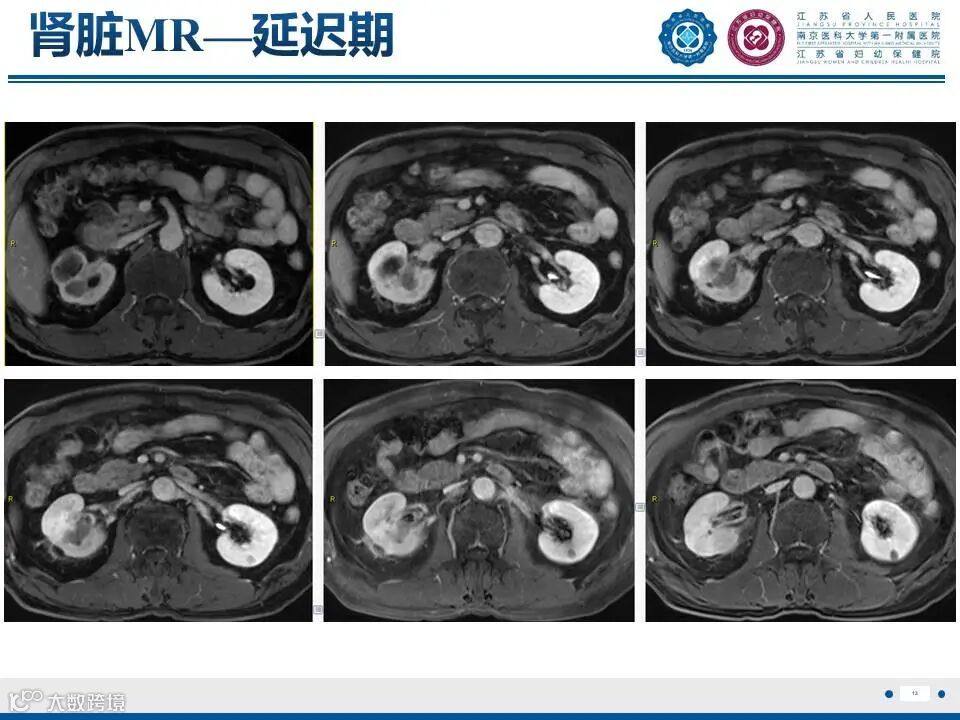

肾实质肾盂尿路上皮癌——水泄不通 II

肾实质肾盂尿路上皮癌——水泄不通 II 鼎湖影像